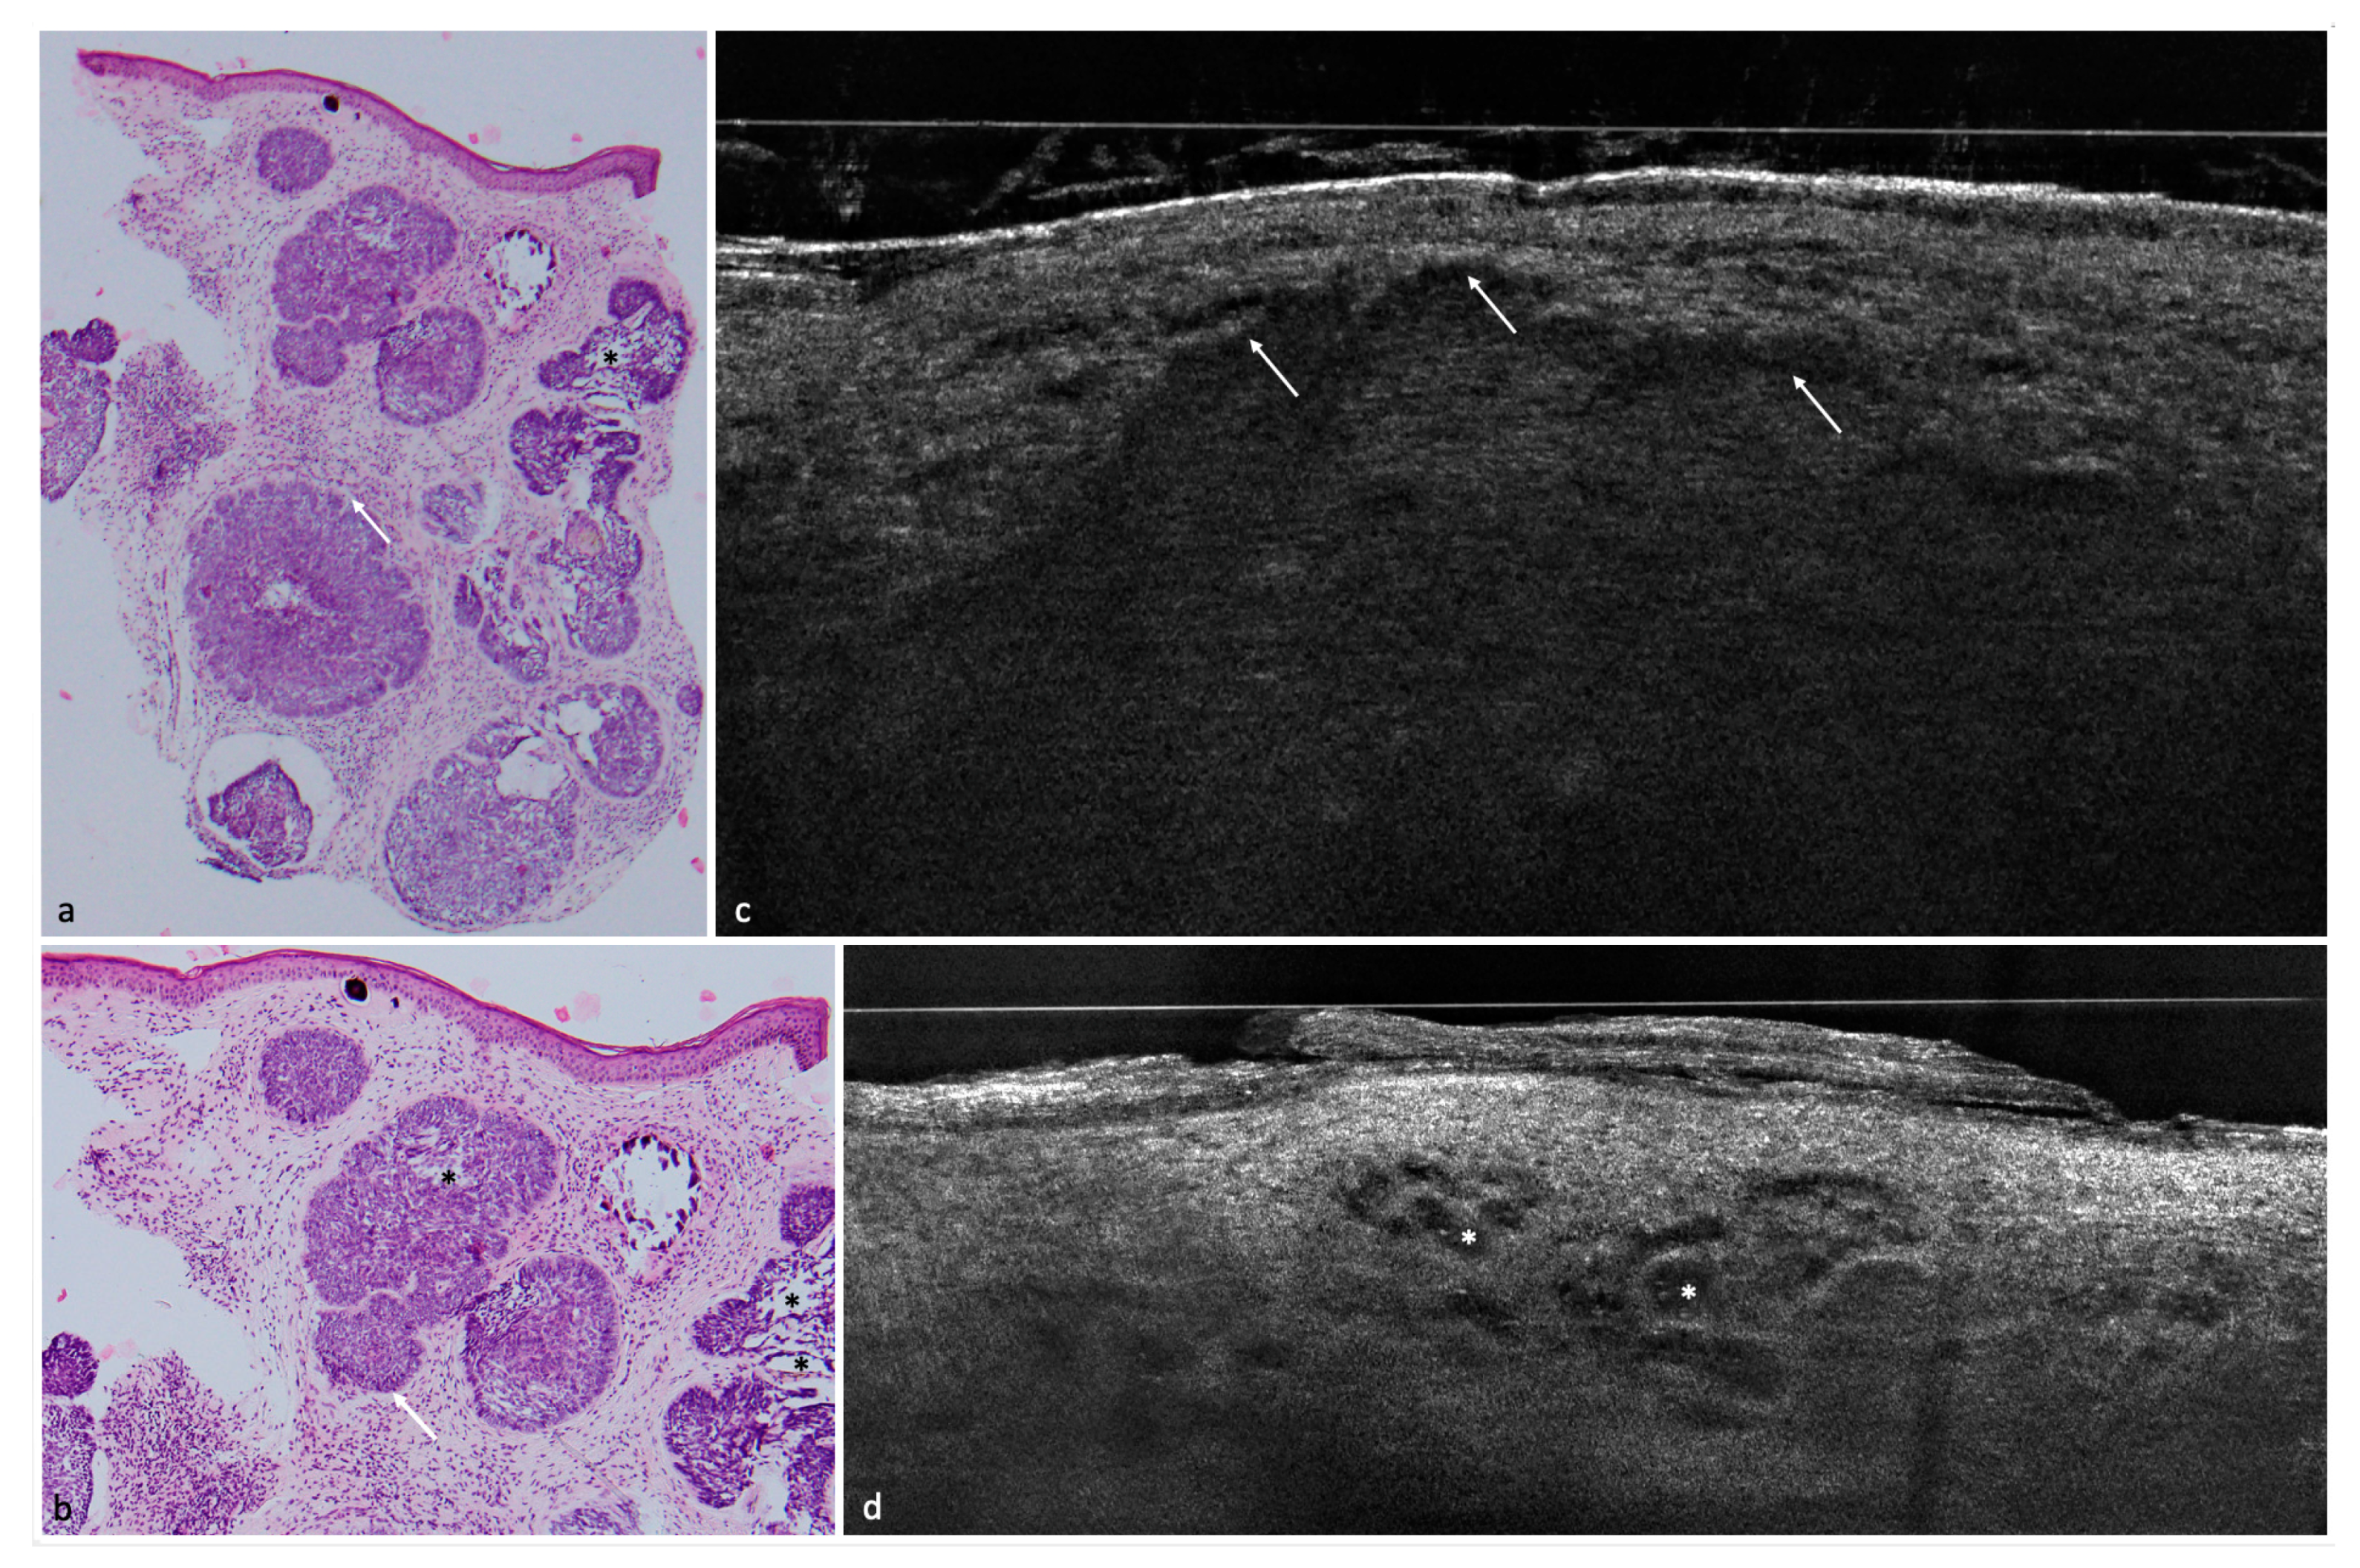

Figure 1. Nodular BCC on the lower leg of a 68-year-old female patient. (a,b) LC-OCT images. The nodular BCC presents itself with a fine granular texture corresponding to basaloid cells, peritumoral clefting (white arrows) and homogeneous areas with possibly liquefactive necrosis with remaining cell debris (white asterisks). (c) (40×), (d) (100×), and (e) (100×): corresponding histological HE-stained sections with peripheral palisading, clefting, and a central necrosis.